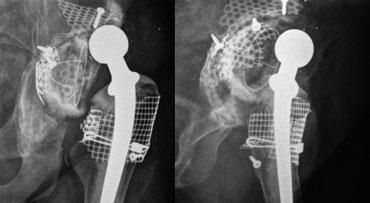

Di lệch cấu phần có giá trị chẩn đoán tình trạng lỏng khớp.

Biểu hiện là sự nghiêng hoặc di lệch lên trên của ổ cối nhân tạo, hoặc sự lún xuống (>10mm) và nghiêng varus của cán khớp háng.

Trường hợp bên trái cho thấy tình trạng lún xuống tiến triển, có giá trị chẩn đoán tình trạng lỏng khớp, kèm theo gãy vít tiếp theo sau đó.

Lỏng khớp (2)

Vì sự di chuyển có thể rất tinh tế, cần so sánh cẩn thận với phim chụp sau phẫu thuật ban đầu.

Không chỉ so sánh với lần khám trước đó.

Trường hợp bên trái cho thấy sự di chuyển của chỏm acetabulum, điều này sẽ được nhận thấy rõ hơn nếu sử dụng một điểm tham chiếu (xem hình tiếp theo)

Trong quá trình theo dõi, sự di chuyển lên trên kèm theo độ nghiêng tăng dần được ghi nhận, gây ra gãy vít cố định.